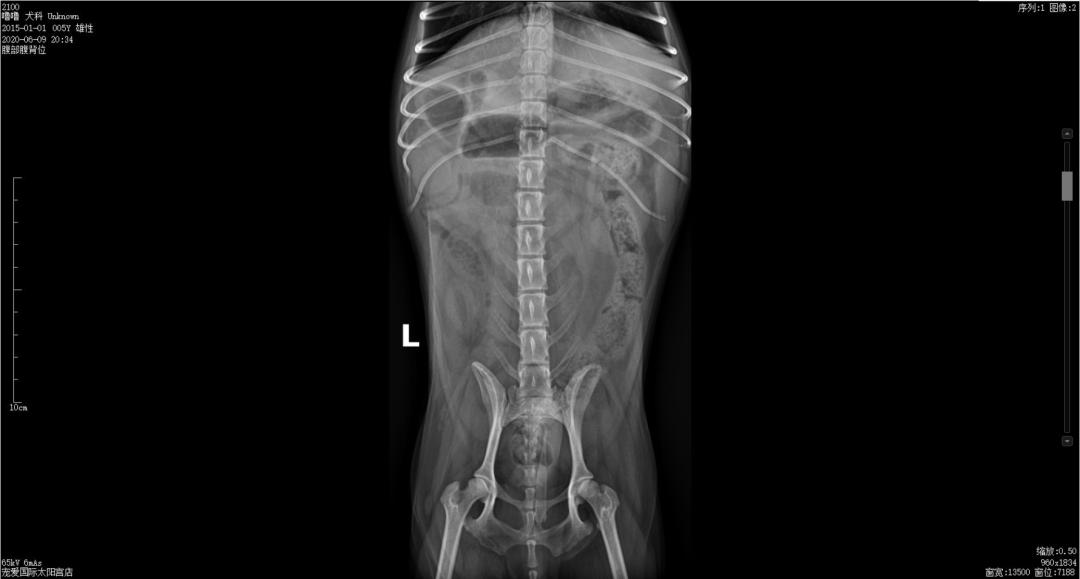

X光检查↓↓

杆状升高,C反升高,提示机体存在炎症,淀粉酶下降无实际意义,DR检查小肠前段有扩张和积气,未见明显异物,结合临床症状及辅助检查,初步怀疑肠道异物。